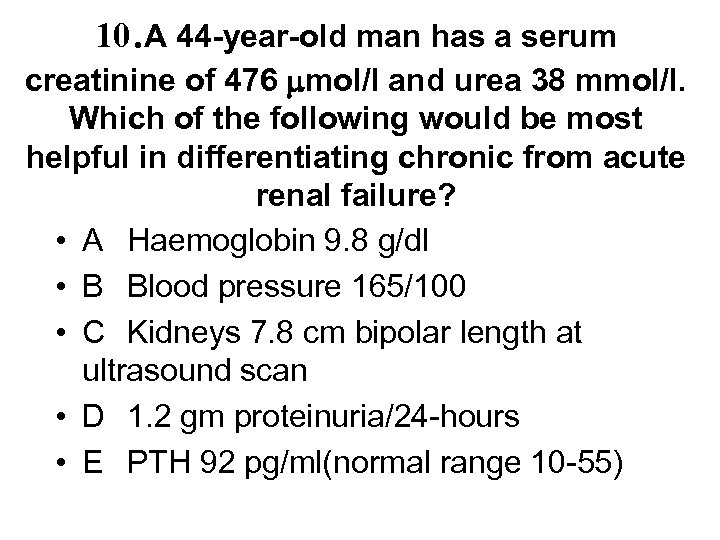

10. A 44 -year-old man has a serum creatinine of 476 mol/l and urea 38 mmol/l. Which of the following would be most helpful in differentiating chronic from acute renal failure? • A Haemoglobin 9. 8 g/dl • B Blood pressure 165/100 • C Kidneys 7. 8 cm bipolar length at ultrasound scan • D 1. 2 gm proteinuria/24 -hours • E PTH 92 pg/ml(normal range 10 -55)

10. A 44 -year-old man has a serum creatinine of 476 mol/l and urea 38 mmol/l. Which of the following would be most helpful in differentiating chronic from acute renal failure? • A Haemoglobin 9. 8 g/dl • B Blood pressure 165/100 • C Kidneys 7. 8 cm bipolar length at ultrasound scan • D 1. 2 gm proteinuria/24 -hours • E PTH 92 pg/ml(normal range 10 -55)

10. A 44 -year-old man has a serum creatinine of 476 mol/l and urea 38 mmol/l. Which of the following would be most helpful in differentiating chronic from acute renal failure? • A Haemoglobin 9. 8 g/dl • B Blood pressure 165/100 • C Kidneys 7. 8 cm bipolar length at ultrasound scan • D 1. 2 gm proteinuria/24 -hours • E PTH 92 pg/ml(normal range 10 -55)

10. A 44 -year-old man has a serum creatinine of 476 mol/l and urea 38 mmol/l. Which of the following would be most helpful in differentiating chronic from acute renal failure? • A Haemoglobin 9. 8 g/dl • B Blood pressure 165/100 • C Kidneys 7. 8 cm bipolar length at ultrasound scan • D 1. 2 gm proteinuria/24 -hours • E PTH 92 pg/ml(normal range 10 -55)

Chronic v acute renal failure • Chronic Haemoglobin Blood pressure Renal size Proteinuria Calcium and PO 4 PTH • Acute • usually anaemic but not ADPKD • HT if glomerular • usually small* • none to heavy if glomerular • usually low Ca with high PO 4 • variable - high in 2 y hyperpara • may become anaemic quickly • HT if RPGN • normal • none to heavy if RPGN • usually low Ca with high PO 4 • variable - can be high *Normal kidney length >10 cms on sonar, borderline 9 -10 cms, small <9 cms, unequal if >1. 5 cms difference, but patients with CRF can have normal size kidneys

Chronic v acute renal failure • Chronic Haemoglobin Blood pressure Renal size Proteinuria Calcium and PO 4 PTH • Acute • usually anaemic but not ADPKD • HT if glomerular • usually small* • none to heavy if glomerular • usually low Ca with high PO 4 • variable - high in 2 y hyperpara • may become anaemic quickly • HT if RPGN • normal • none to heavy if RPGN • usually low Ca with high PO 4 • variable - can be high *Normal kidney length >10 cms on sonar, borderline 9 -10 cms, small <9 cms, unequal if >1. 5 cms difference, but patients with CRF can have normal size kidneys